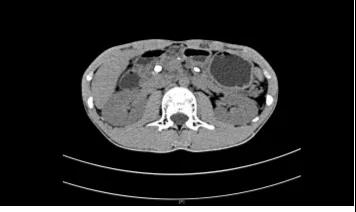

查了腹部CT,

结果提示:

胰管多发结石,

伴胰管不均匀扩张,

胰腺实质萎缩,

经过详细的术前检查,医生发现小黄整个胰管充满结石,尤其是胰头部及胰尾部主胰管和分支胰管均有大量结石,胰体部主胰管有结石而分支胰管结石少。

(术前CT图)